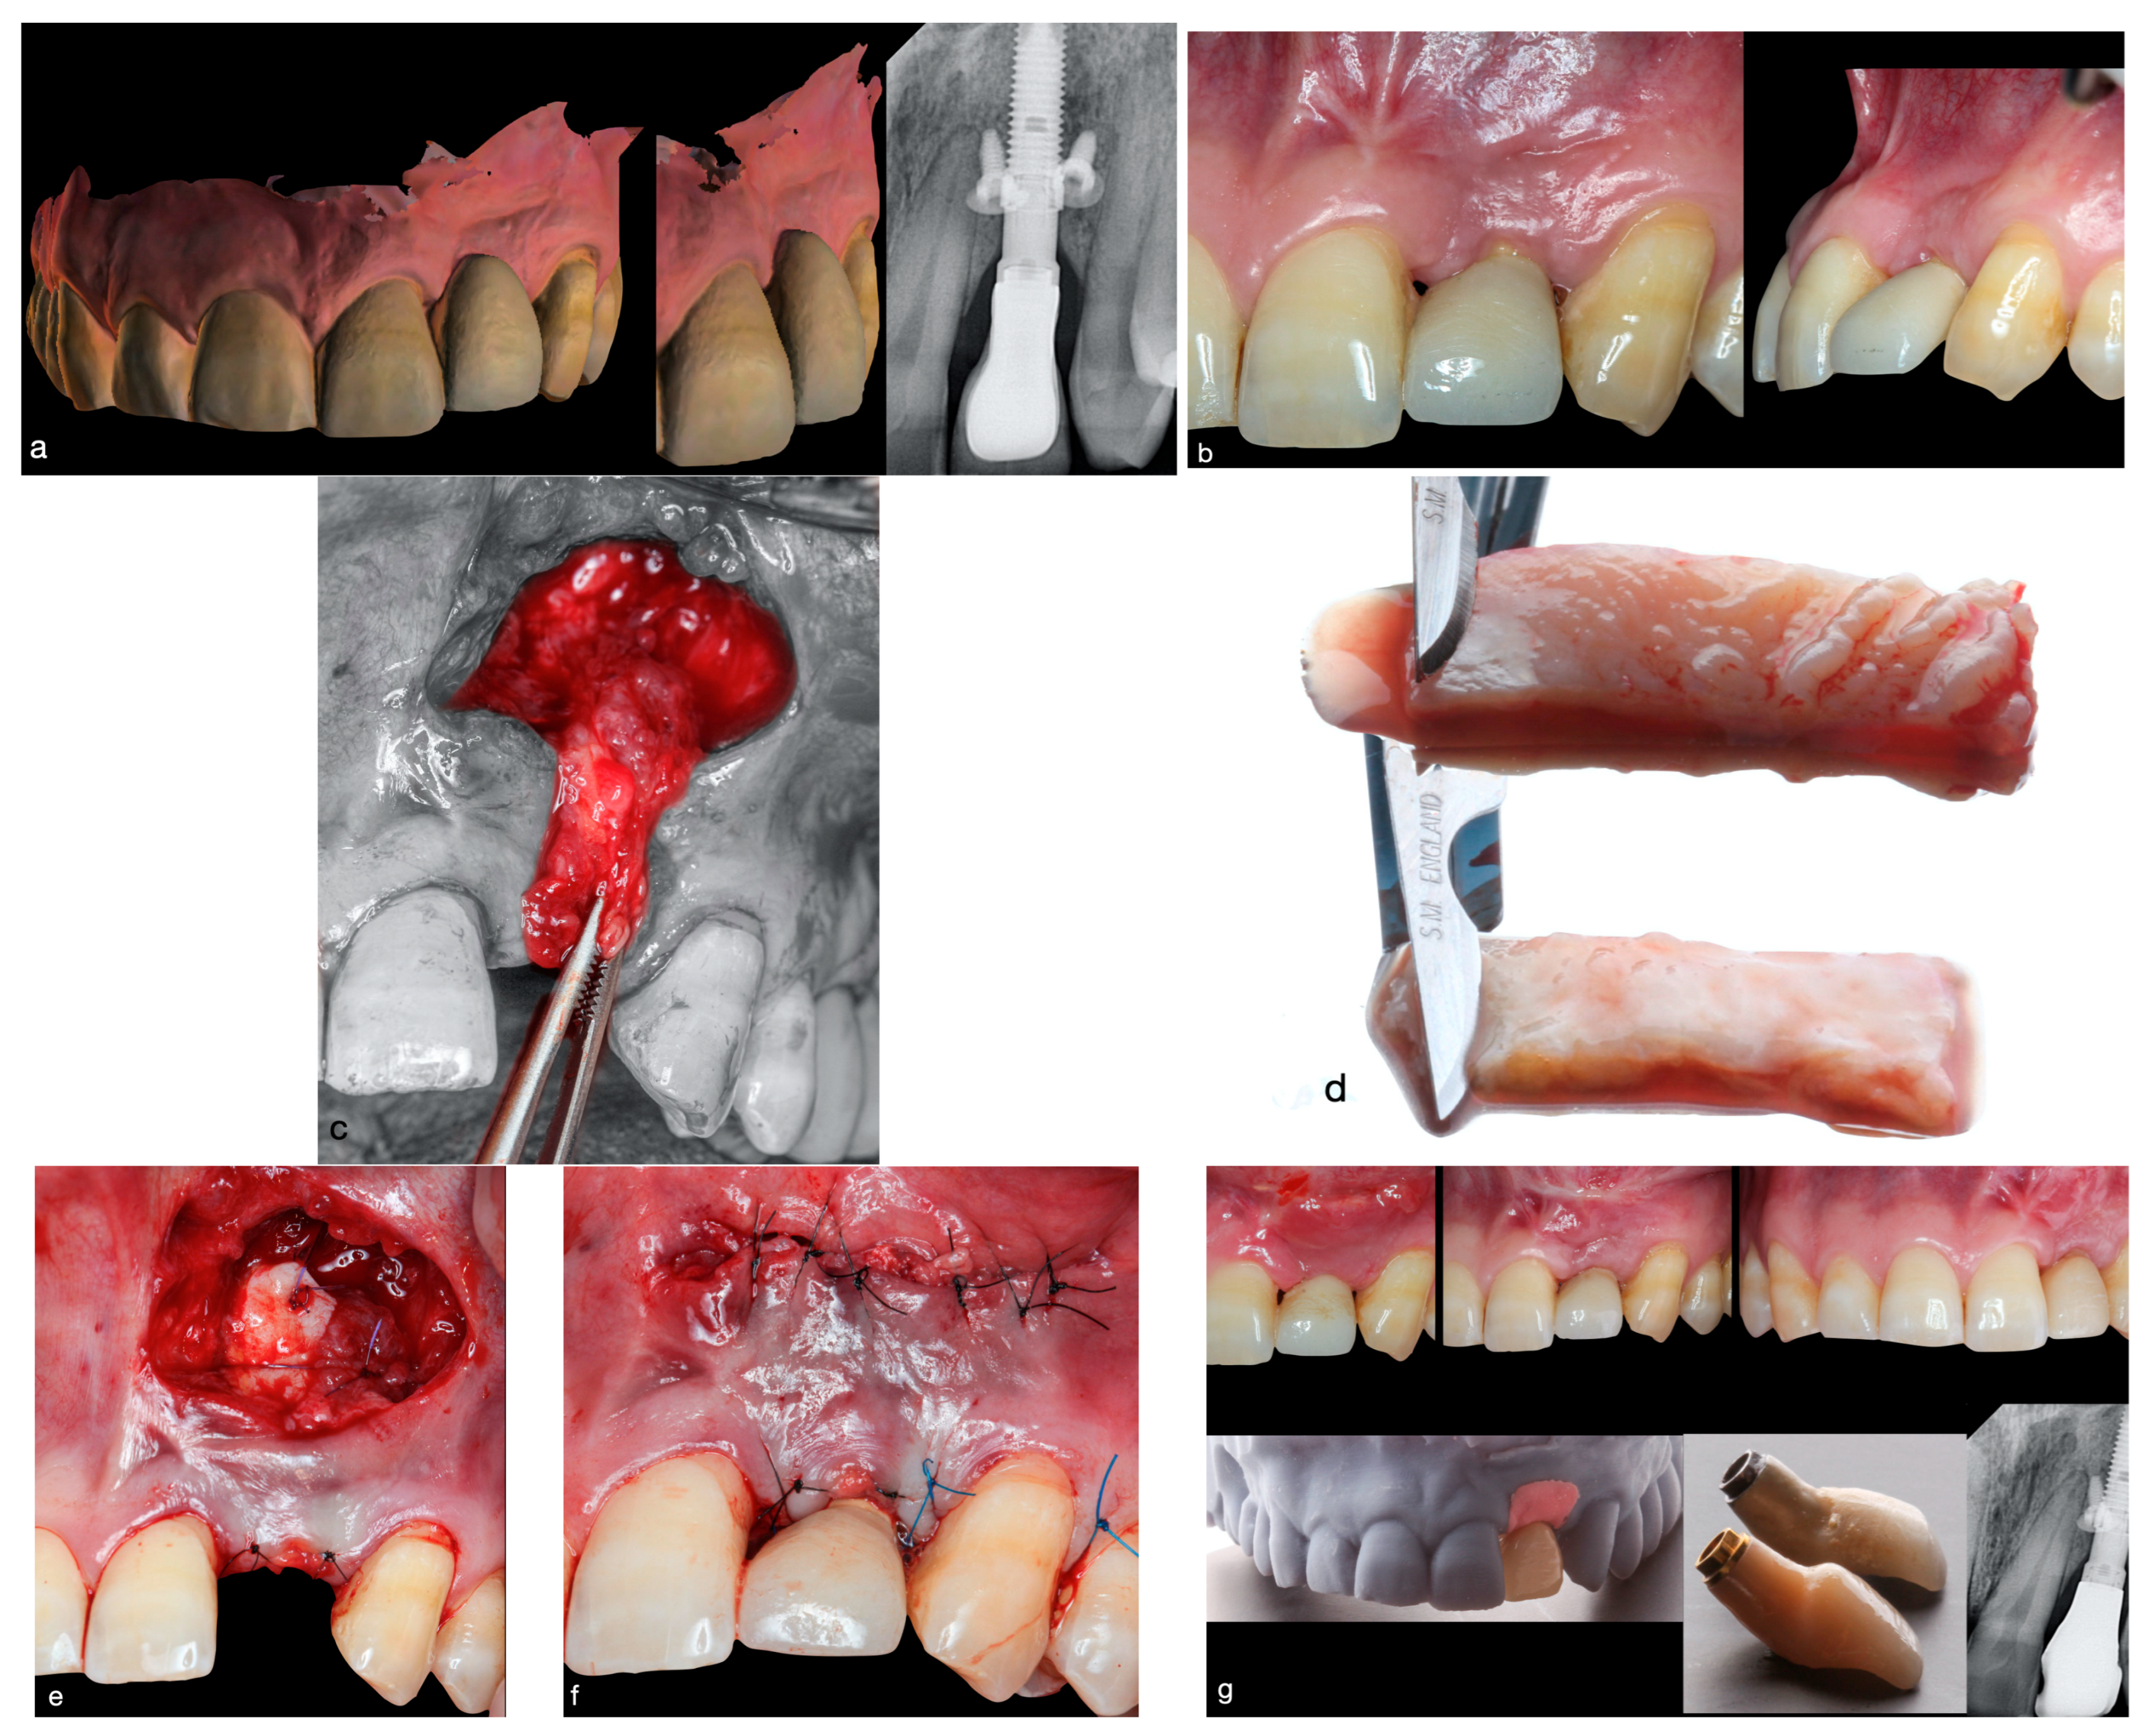

2.1.2. Surgical Procedure

2.1.3. Preparing the Recipient Site

2.1.4. Preparing the Connective Tissue Pedicle Graft

2.1.5. Harvesting the De-Epithelialized Free Gingival Graft

2.1.6. Graft Placement